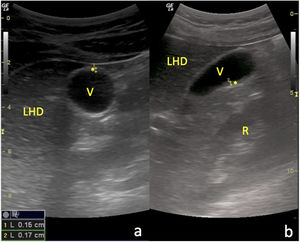

En este contexto, se presenta el caso de una adolescente de 12 años con dolor en epigastrio e hipocondrio derecho, astenia, fiebre y vómitos de 72h de evolución. La ecografía clínica mostró engrosamiento mural vesicular en «capas de cebolla» de hasta 8mm (normal <3mm), sin cálculos ni barro biliar, y sin flujo en Doppler color (fig. 1 y vídeo). Fue remitida al hospital, donde se objetivaron hipertransaminasemia, hiperbilirrubinemia y serología positiva para el VHA, diagnosticándose CAA asociada al VHA. El tratamiento conservador logró la resolución completa clínica, analítica y ecográfica (fig. 2).

Resolución estructural de la CAA: a) Corte transversal del abdomen a nivel de hipocondrio derecho con sonda convex, en el que se objetiva una sección axial de la VB con pared de morfología y grosor normales (*); b) Corte longitudinal paramedial del abdomen con la misma sonda y al mismo nivel que el anterior, en el que se visualiza una sección sagital de la VB con pared igualmente normal (*). LHD: lóbulo hepático derecho; R: riñón derecho.